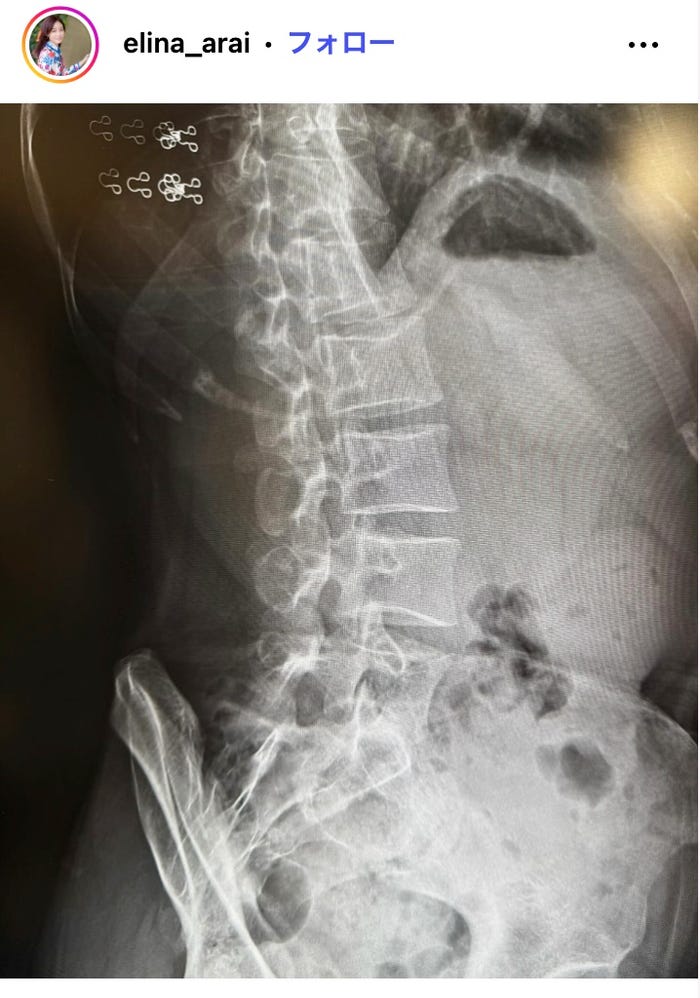

フリーアナウンサーの新井恵理那が12月2日、自身のInstagramを更新。病院で診察を受けた際のレントゲン写真を公開し、反響を呼んでいる。

新井は「ヘルニアではありませんでしたが はじめて、所謂ぎっくり腰になりました」とつづり、自身の横向きのレントゲン写真を公開。「ソファに座る長男に『どれにする?』と絵本を差し出した瞬間」に発症したといい、「どうしたらいいの!?とパニックになりましたが、腰痛に詳しい友人がいろいろ教えてくれました 笑」と当時を振り返った。現在はコルセットと理学療法で対処しているとも説明し、「座りっぱなしでの仕事が立て続いたためダメージが蓄積されていたのかな?下の子も大きく重くなってきたからなおさらかもしれません」と原因についても心当たりを明かしている。新井恵理那の投稿に反響